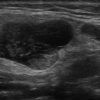

U tuyến nước bọt

» Thông tin: Nam giới – 71 tuổi.

» Lâm sàng: Khối vùng mang tai.

# U lympho tuyến nang (U Warthin) tuyến nước bọt mang tai.